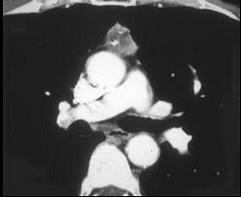

问题 男,45岁,胸骨后隐痛伴四肢无力3月余,请结合影像学检查,选出最可能的诊断 ( )

选项 A、淋巴瘤 B、间皮囊肿 C、纵隔畸胎瘤 D、胸腺瘤 E、胸内甲状腺肿

答案 D